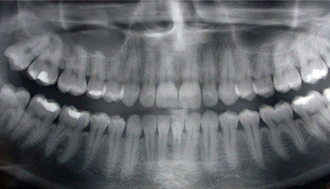

At Venkateshwar Hospital, we embrace the latest advancements in digital dentistry to improve the accuracy and efficiency of our treatments. Our digital dentistry services include digital X-rays, 3D imaging, and computer-aided design and manufacturing (CAD/CAM) technology. These innovations enable us to provide precise diagnoses, customized treatment plans, and high-quality restorations, all while minimizing discomfort and reducing treatment time.

Diagnosis, Implant planning & follow-up of implants. It can also be used for accurate measurement of dimension of lesions & planning of surgical procedures.

- Cubical Semi Tomography

- Advanced CMOS Sensor

- Face to Face Positioning

- With Floor Stand